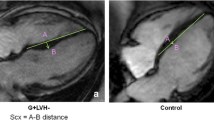

Retro-triggered, balanced steady-state free precession (SSFP) short-axis cine imaging with full coverage of the LV was acquired for quantification of LV volumes, mass and ejection fraction (EF) (Figure 1). Image parameters were: slice thickness 5 mm, slice gap 5 mm, temporal resolution <50 ms, 20 phases per cardiac cycle, echo time 1.54 ms, repetition time 3.2 ms, flip angle 60 degrees and a typical image resolution of 1.3*1.6 mm. For analysis of left atrial (LA) volume, the same acquisition was performed in a transversal orientation, planned on an end-diastolic 2-chamber view at the level of the lower leading edge of the mitral valve annulus as described previously [29]. The LA was subsequently fully covered by a stack of transversely oriented slices.

CMR techniques used for morphological and functional assessment. A: End-diastolic basal short-axis SSFP image of a healthy control, used for quantification of LV volumes and mass. B: LV basal short-axis end-diastolic HARM-image of the same patient as (A) with manually drawn epicardial (green) and endocardial (red) contours. By using Harmonic phase (HARP) analysis, myocardial deformation can be monitored throughout the cardiac cycle, allowing determination of left ventricular torsion and subendocardial circumferential strain (inner 50% of the LV wall) throughout the cardiac cycle. C: End-diastolic short axis SSFP image of a HCM mutation carrier, showing normal cardiac morphology and dimensions. D: LV short axis HARM-image of the same carrier as (C) acquired at end-systole.

Myocardial tissue tagging (Figure 1) was performed at three short-axis slices, located at ¼ (base), 1/2 (mid), and ¾ (apex) of the length between the mitral valve and the apex, planned on an end-systolic four-chamber image. Sinusoidal, complementary tagged (CSPAMM) images were acquired with a retro-triggered SSFP sequence using a multiple brief expiration breath hold scheme [31]. Temporal resolution was 15 ms. The imaging parameters were as follows: field of view: 300 × 300 mm2, flip-angle: 20°, repetition time: 3.6 ms, echo time: 1.8 ms, receiver bandwidth: 850 Hz/pixel, matrix size: 256 × 78, slice thickness: 6 mm, tag-line distance: 7 mm. Acquisition time per slice was approximately 3-4 minutes. After tagging images were derived, we administered 0.2 mmol/kg Gadolinium-DTPA (Magnevist, Schering©) solely to the HCM mutation carriers, in order to obtain Late Gadolinium Enhancement (LGE) images for the detection of intramyocardial fibrosis.

From the tagging images, LV torsion was calculated as the circumferential-longitudinal shear angle using Harmonic Phase displacement tracking as described before [32, 33]. For this, endo- and epicardial contours were drawn on the harmonic magnitude (HARM) images (Figure 1) [34]. Since this method includes the radius and the length of the ventricle, torsional values are comparable between hearts of different sizes. Torsion was calculated between the basal and apical slices, between the basal and mid slices and between the mid and apical slices.

Furthermore, Lagrangian circumferential strain was calculated from the tagging images using the Harmonic Phase method as described previously [36]. Strains were assessed for the inner (subendocardial) layer of the myocardium, encompassing 50% of the LV wall. Therefore, the epicardial contour (green line in Figure 1) was automatically shifted towards the centre of the wall. Peak values were determined from the strain curves.